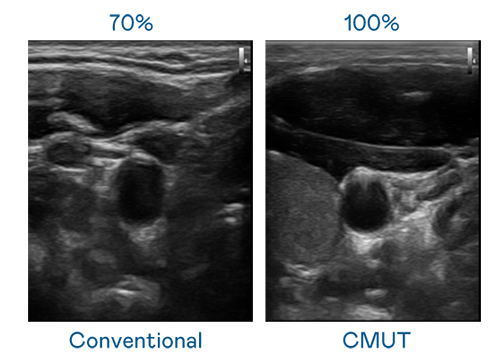

CMUT 技术是一种用电容式微机电元件来产生超音波讯号的技术。与传统 PZT 压电式技术相比,CMUT 频宽增加 30%,更宽频的超音波讯号让影像解析度大幅提升,是实现高影像品质医疗超音波扫描、促进精准医疗发展的关键技术。

大频宽带来超清晰影像

超音波影像的解析度高低,首先取决于探头能发出的讯号频宽。yd12399云顶 CMUT 可提供高清晰的超音波讯号,提供高频宽、高灵敏度、影像纹理细节更高的超音波影像,协助医护人员缩短影像判读时间及利用精准的医疗影像进行诊断。